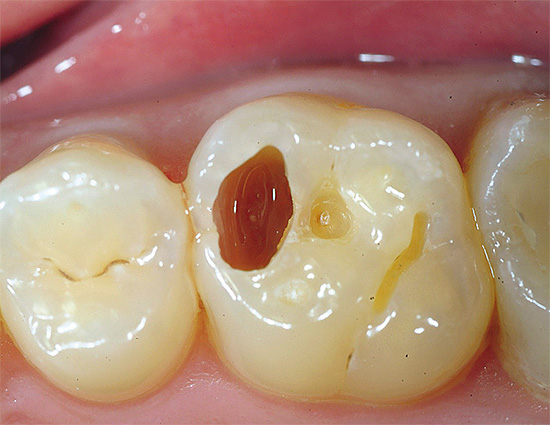

O último estágio do desenvolvimento do processo carioso envolve a proximidade de tecidos dentários danificados e infectados a uma polpa saudável ("nervo"). Como resultado disso, sempre existe o risco de confusão entre cáries profundas e o aparecimento de complicações na polpa de um dente quando uma infecção cariada entra nele. Portanto, nesses casos, o tratamento deve ser realizado somente após um diagnóstico detalhado da etapa do processo.

Nesse caso, a dentina amolece devido à liberação de componentes minerais (cálcio, fósforo, compostos de flúor), seguida pela dissolução da matéria orgânica (colágeno) sob a ação de enzimas bacterianas. A formação de uma cavidade como cárie média com dentina infectada amolecida, sem tratamento, leva inevitavelmente a um aprofundamento do processo patológico e a um aumento na área de destruição. Se nesta fase você não tratar cáries profundas, poderá perder tempo e haverá uma complicação na transição da infecção para tecido pulpar não protegido ("nervo") dentro do dente.

Os principais sintomas de cárie profunda

Antes de tratar a cárie profunda, o dentista examina cuidadosamente as queixas do paciente, pois nesta fase já é possível confirmar ou negar o diagnóstico.

Se coletarmos estatísticas de histórias de casos de cárie profunda, entre as queixas mais comuns e seus recursos, será possível distinguir o seguinte:

- Dor causada por irritantes da temperatura (quente e fria), química (principalmente doce) e mecânica (quando alimentos sólidos entram na cavidade).

- Natureza de curto prazo da dor. A dor desaparece rapidamente após a eliminação do irritante.